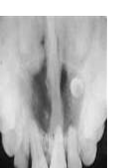

nasopalatine canal cyst

-40-60yr men>women -asymptomatic pink bulge at the incisive papillae area well circumscribed radiolucency between the maxillary central incisors -HEART SHAPED